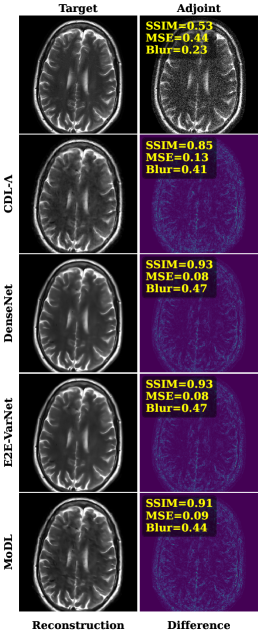

Comparison to Other Methods: Figure 4 shows a visual comparison of the adjoint reconstruction, MoDL, E2E VarNet, SRDenseNet, and the investigated CDL-𝚲\boldsymbol{\Lambda} using K=64K=64 filters of size kf×kf=11×11k_{f}\times k_{f}=11\times 11 for a brain and knee MR image, together with their respective error images and image metrics.

Refer to caption

Fig. 4: A comparison of MoDL [1], E2E VarNet [19], SRDEnseNet [7] and CDL-𝚲\boldsymbol{\Lambda} method (K=64,11×11K=64,11\times 11-kernels) on in-distribution brain MR data (left, σ2=0.3\sigma^{2}=0.3) and out-of-distribution knee MR data (right, σ2=0.2\sigma^{2}=0.2).

Despite yielding accurate reconstructions, CDL-𝚲\boldsymbol{\Lambda} is surpassed by all other learned methods. However, when tested on out-of-distribution data, i.e., on the knee images, the performance gap between the different methods is noticeably reduced. For example, compare the reduced difference between MoDL and CDL-𝚲\boldsymbol{\Lambda} in terms of SSIM for brain vs knee images, for σ2=0.2\sigma^{2}=0.2 and σ2=0.3\sigma^{2}=0.3 in Figure 5.